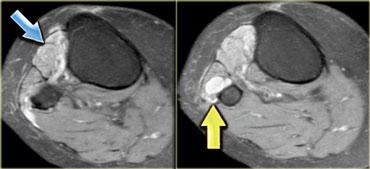

Hình bên trái là một bệnh nhân viêm cơ thể vùi.

Lưu ý tổn thương đối xứng của cơ tứ đầu đùi và sự vắng mặt của phù nề ở các tổ chức xung quanh.